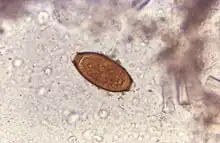

Adult worms are usually 3–5 centimetres (1.2–2.0 in) long, with females being larger than males as is typical of nematodes. The thin, clear majority of the body (the anterior, whip-like end) is the esophagus, and it is the end that the worm threads into the mucosa of the colon. The widened, pinkish gray region of the body is the posterior, and it is the end that contains the parasite's intestines and reproductive organs. T. trichiura eggs are prolate spheroids, the shape of the balls used in Rugby and Gridiron football. They are about 50–54 μm (0.0020–0.0021 in) long and have polar plugs (also known as refractile prominences) at each end.

A stool ova and parasites exam reveals the presence of typical whipworm eggs. Typically, the Kato-Katz thick-smear technique is used for identification of the Trichuris trichiura eggs in the stool sample. Trichuria eggs often appear larger and more swollen on Kato-Katz preparation compared to when using other techniques.[18]

Trichuriasis can be diagnosed when T. trichiura eggs are detected in stool examination. Eggs will appear barrel-shaped and unembryonated, having bipolar plugs and a smooth shell.[19] Rectal prolapse can be diagnosed easily using defecating proctogram and is one of many methods for imaging the parasitic infection. Sigmoidoscopys show characteristic white bodies of adult worms hanging from inflamed mucosa ("coconut cake rectum").